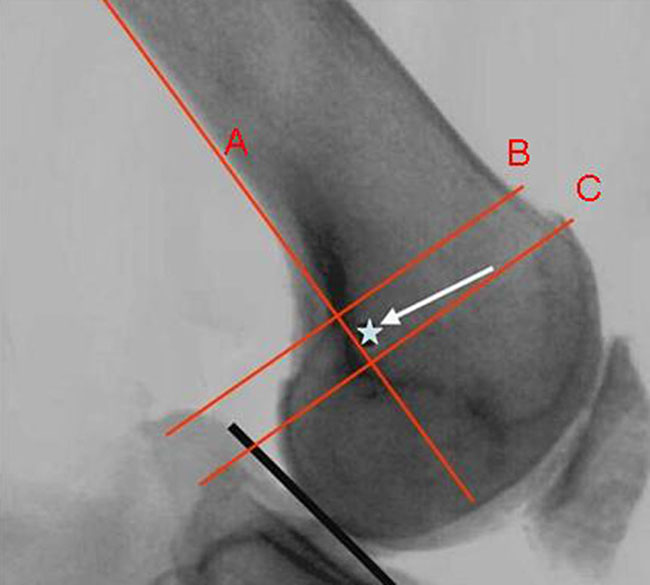

Se utiliza intensificador de imágenes para ubicar el punto preciso de inserción del LPFM. Para ubicarlo es importante colocar la rodilla en un estricto perfil. El lugar de colocación del túnel femoral es ligeramente anterior a una línea que pasa por la cortical posterior y se ubica entre dos líneas perpendiculares a esta última: una que pasa por el punto más posterior de la línea de Blumensaat y la otra por el punto de unión del cóndilo interno y la cortical posterior (Fig. 3).22

Figura 3: Ubicación del túnel femoral. La línea A marca la cortical femoral posterior y dos líneas perpendiculares, B a través del punto de unión cóndilo con la cortical posterior y C el punto más posterior de la línea de Blumenssat.